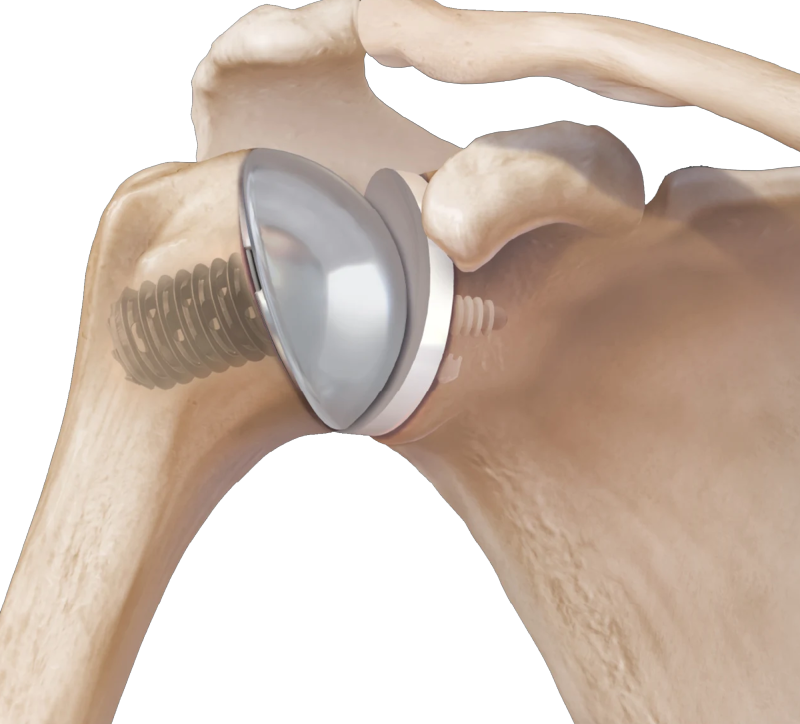

Resurfacing shoulder arthroplasty is a specialized form of shoulder replacement surgery that focuses on replacing only the damaged surface of the humeral head (the ball of the shoulder joint) instead of the entire joint. At our Delhi orthopedic center, our experienced surgeons offer this advanced procedure for patients who need pain relief and improved mobility while preserving as much natural bone as possible.

Unlike total shoulder replacement, which replaces both the ball and socket, resurfacing shoulder arthroplasty involves capping the damaged ball of the joint with a smooth, metal prosthesis. This approach is less invasive, preserves more bone, and is often ideal for younger, active patients with localized joint damage.